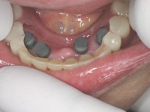

両側5歯症例

両側5歯症例両側5歯症例両側5歯症例 主訴-義歯のバネが壊れて手前の歯が痛んできた。 術前(旧義歯装着、鏡像) 術前(下顎粘膜面、鏡像)術前(下顎粘膜面、鏡像)術前(下顎粘膜面、鏡像) 術前レントゲン術前レントゲン術前レントゲン 術前口腔内(正面観)術前口腔内(正面観)術前口腔内(正面観)